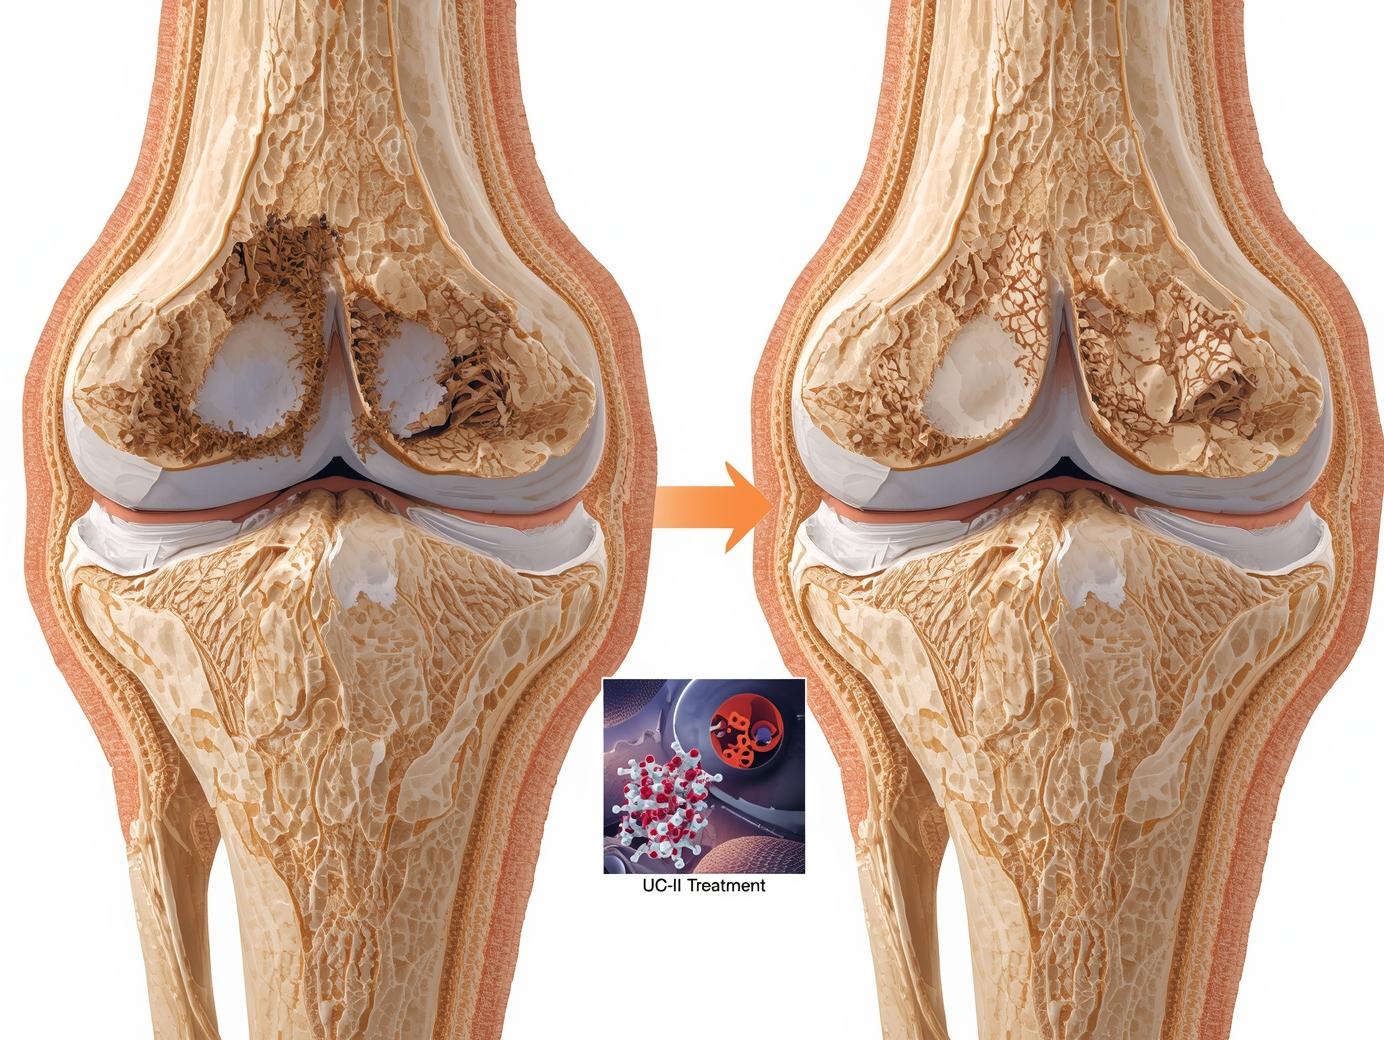

- غضروف مفصلی: کاهش تخریب غضروف، کاهش اندازه استئوفیت ها و حفظ ماتریکس غضروف در گروه UC- II مشاهده شد.

- استخوان زیرغضروفی : UC-II از کاهش تراکم استخوان اسفنجی جلوگیری کرد.

مصرف خوراکی UC-II بلافاصله پس از آسیب، میتواند با حفظ عملکرد مکانیکی مفصل، از تخریب بیش از حد غضروف جلوگیری کند. این یافته ها از کاربرد UC-II به عنوان یک گزینه درمانی کمکی در استئوآرتریت حمایت می کنند.